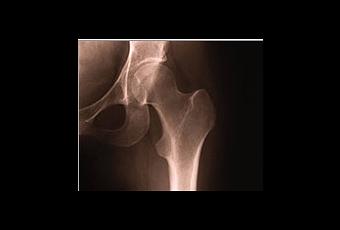

Les taux de mortalité dans les 90 jours suivant la chirurgie de remplacement de la hanche ont diminué de moitié annonce cette étude de l’Université de Bristol, menée sur plus de 400.000 patients britanniques et publiée dans l’édition du 28 septembre du Lancet. Des conclusions très encourageantes d’autant que l’étude identifie les conditions de réduction du risque.

Les chercheurs de Bristol, d’Oxford, d’East Anglia et d’Exeter ont analysé les données de 409.000 patients ayant subi un remplacement de la hanche en raison de l’arthrose entre 2003 et 2011. Leurs conclusions révèlent qu’entre 2003 et 2011, les taux de mortalité dans les 90 jours suivant l’intervention sont réduits de moitié, passant de 0,6% à 0,3%.